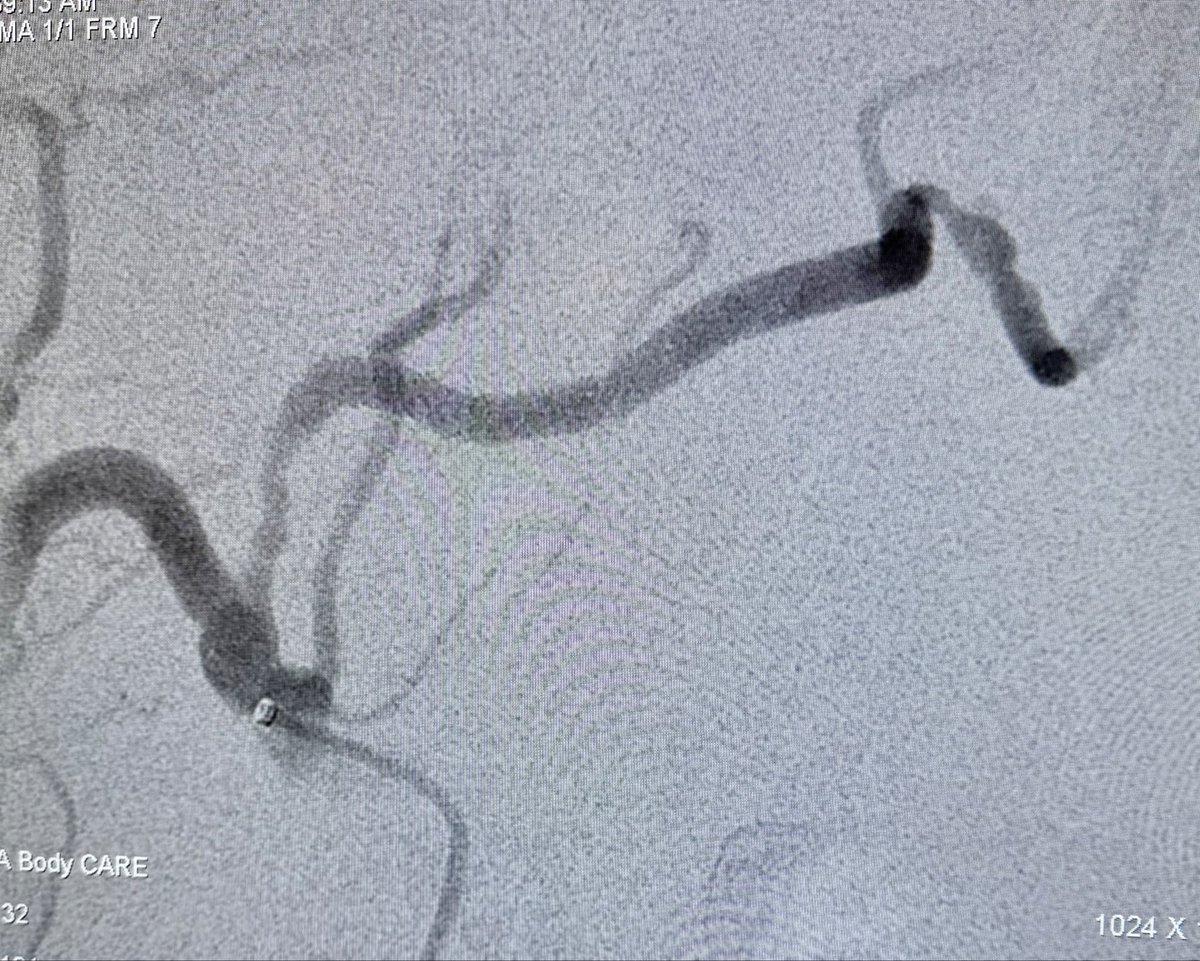

80 hrs of call #rupture #aorta #EVAR x2 #Endoanchors @MDT_Cardiac #DVT @Pen #GSW fem artery